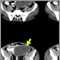

A CT scan of the abdomen will usually reveal an intra-abdominal abscess. After the CT scan is done, a needle may be placed through the skin into the abscess cavity to confirm the diagnosis and treat the abscess.